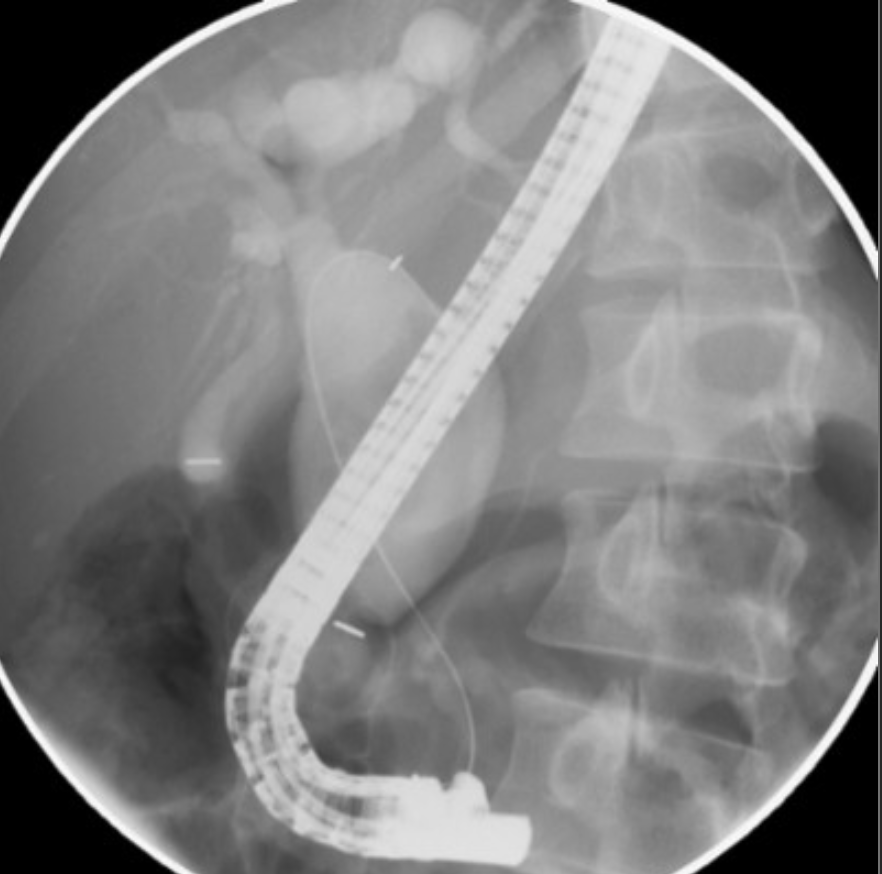

Dx: type 4A choledochal cyst.